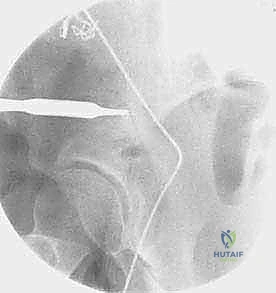

القطع الأول: القطع الإسكي غير المكتمل (Incomplete Ischial Osteotomy)

باستخدام إزميل خاص ذو زاوية (Angled Osteotome)، يتم إجراء قطع في عظم الإسك أسفل الحُق مباشرة (في الأخدود تحت الحُقي). يتم هذا القطع بتوجيه الأشعة السينية (Fluoroscopy) لضمان عدم اختراق المفصل. يحرص الدكتور هطيف على إبعاد العصب الوركي والأوعية السدادية بأمان تام.